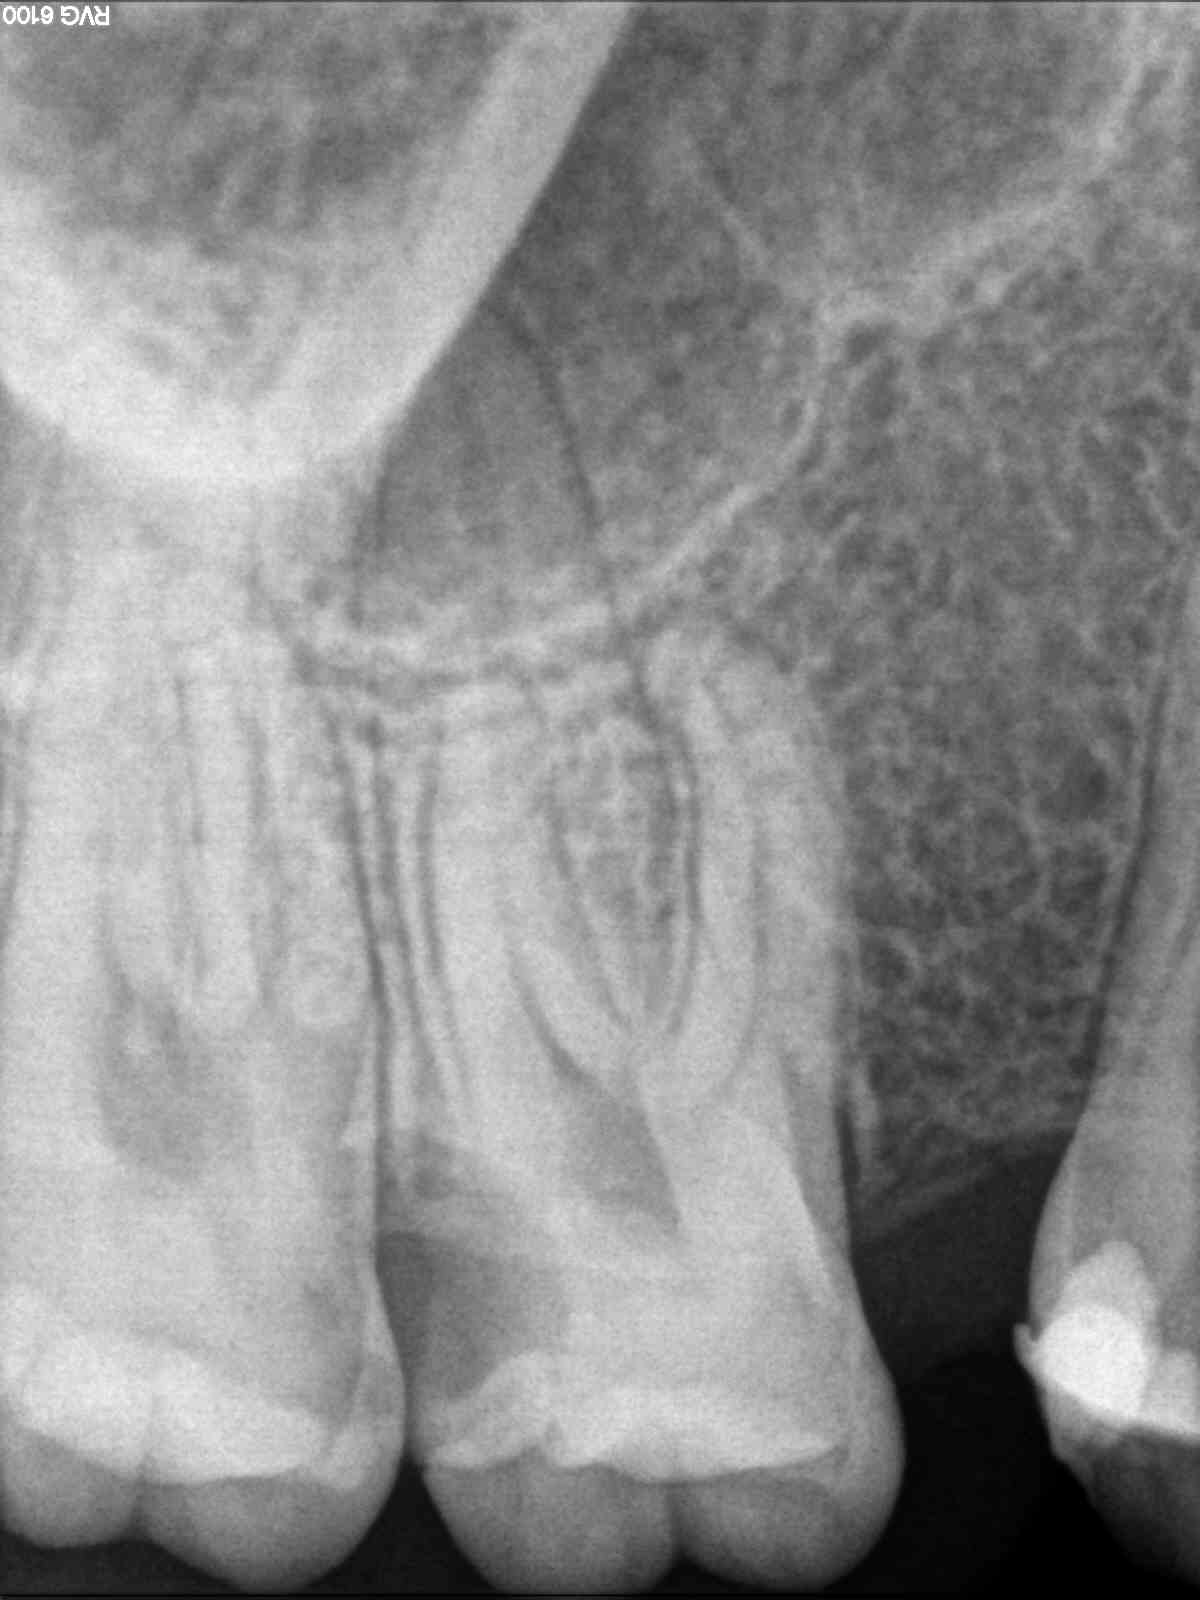

B) Un 1.6 con una pulpitis irreversible.

B)